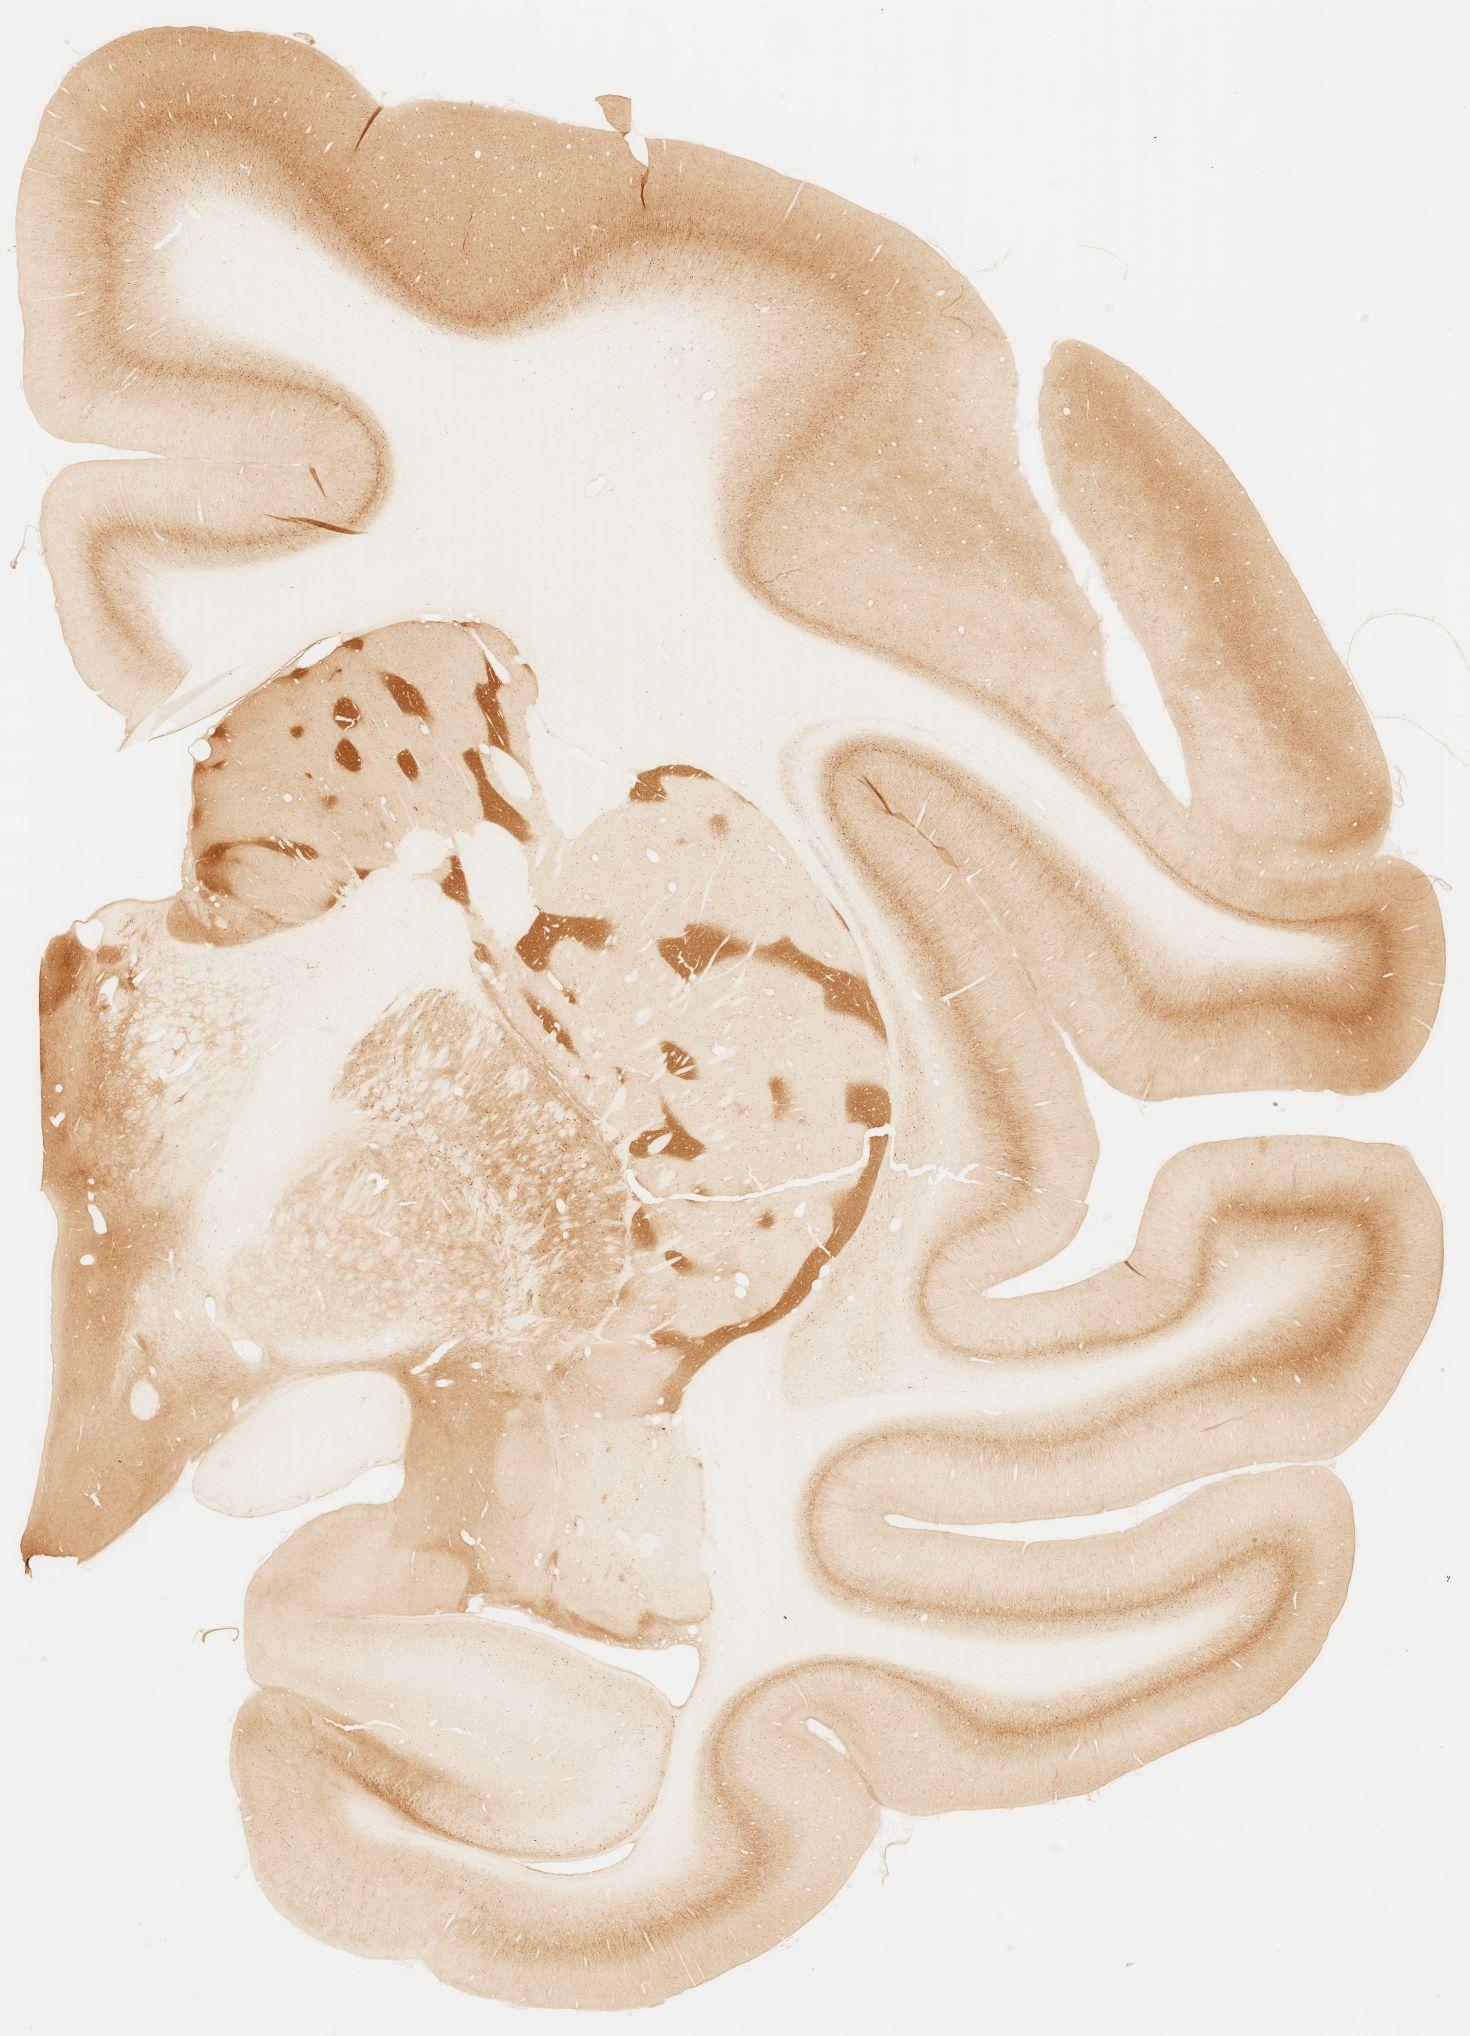

Datasets -> Macaca Fascicularis -> KChIP1, (Potassium Voltage-Gated Channel-Interacting Protein 1), coronal, immuno, Whole-Brain, adult

[ Metadata ]   ·   Source: Edward G. Jones

Displaying Sections 41 thru 80 of 92 Sections for this Dataset